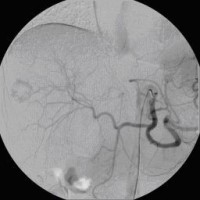

« Zurück Superselektive transarterielle Chemoembolisation (TACE) mit Sondierung eines tumorversorgenden Gefäßes 1 (Bild 3 von 5) Vorwärts »

« Zurück Superselektive transarterielle Chemoembolisation (TACE) mit Sondierung eines tumorversorgenden Gefäßes 2 (Bild 4 von 5) Vorwärts »

« Zurück Superselektive transarterielle Chemoembolisation (TACE) mit Sondierung eines tumorversorgenden Gefäßes 3 (Bild 5 von 5)